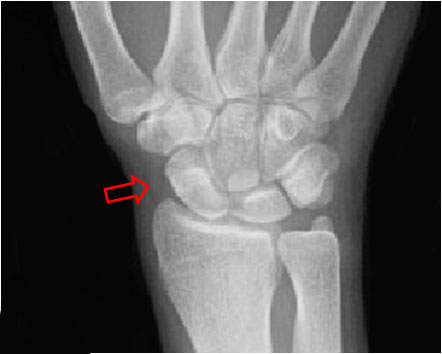

SIGNO DE LA BANDA DEL ESCAFOIDES

La banda adiposa del escafoides es una imagen lineal o triangular de densidad grasa, que se localiza entre el escafoides y las vainas tendinosas del abductor largo y del extensor corto del pulgar. El borramiento o desplazamiento de esta línea se presenta en las fracturas del escafoides, de la apófisis estiloides radial o de la base del primer metacarpiano, aun cuando no se vea la línea de fractura. En el ejemplo puede verse el borramiento de la banda adiposa del escafoides y la fractura de este hueso.

ESCAFOIDES2La flecha marca la banda adiposa del escafoides en una radiografía normal.